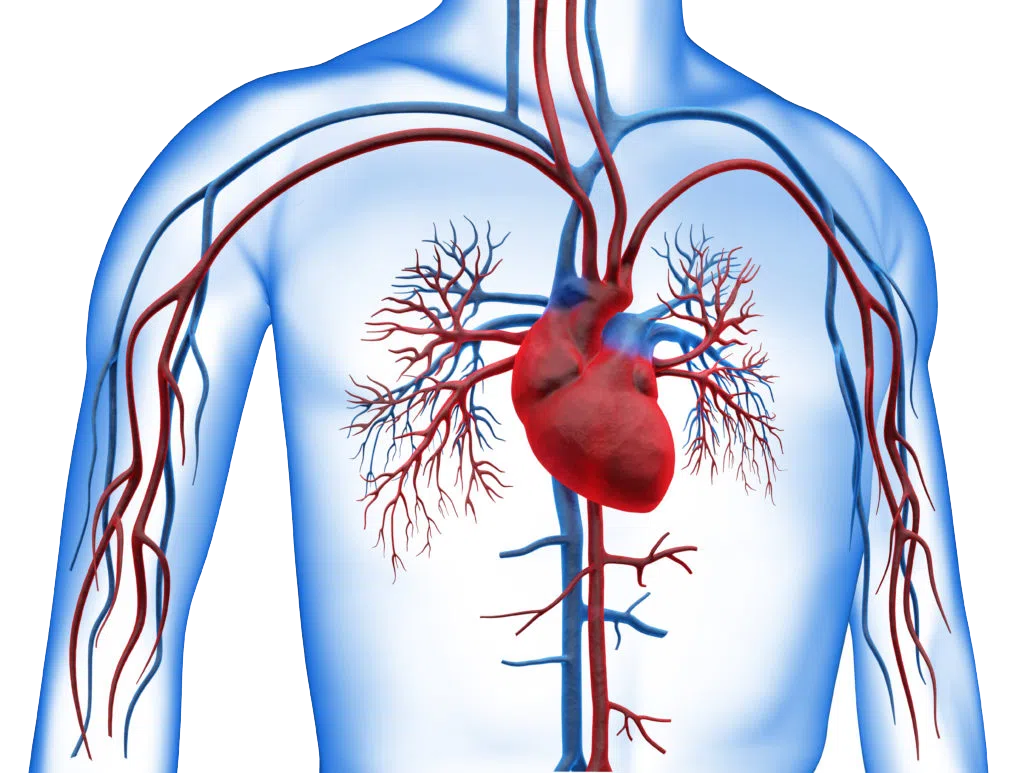

Heart Preload Failure

This study aims to evaluate different explanations of preload failure in ME/CFS patients.